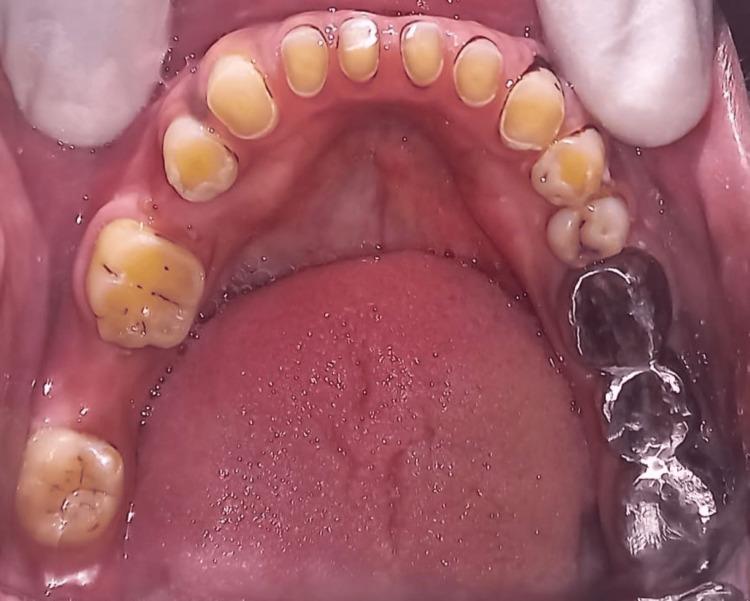

The attachment of a fixed partial denture (FPD) on a pier abutment may be necessary in some partially edentulous instances because of the pattern of lost teeth. Nonetheless, it has been noted that using a stiff FPD to restore two lost teeth and an intermediate pier abutment is not the best course of action. In this case, using a stiff connector concentrates the stresses on the pier abutment. In this situation, the pier abutment serves as a pivot, increasing the debonding of the fixed dental prosthesis and ultimately compromising the success of the FPD. Connectors that are not stiff can solve these issues. A nonrigid connector allows abutments to move independently and distributes shear forces to the supporting bone. Instead of the typical rigid connector, the nonrigid connector serves as a stress breaker between the retainer and the pontic.